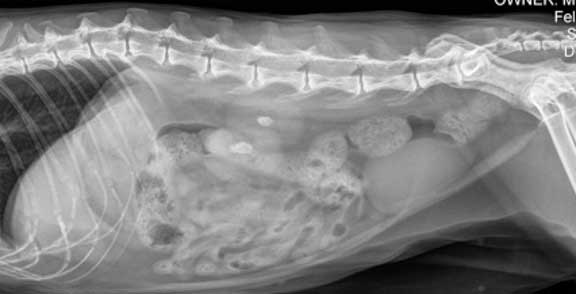

This cat with a large intestine filled with feces is a severe form of constipation called obstipation